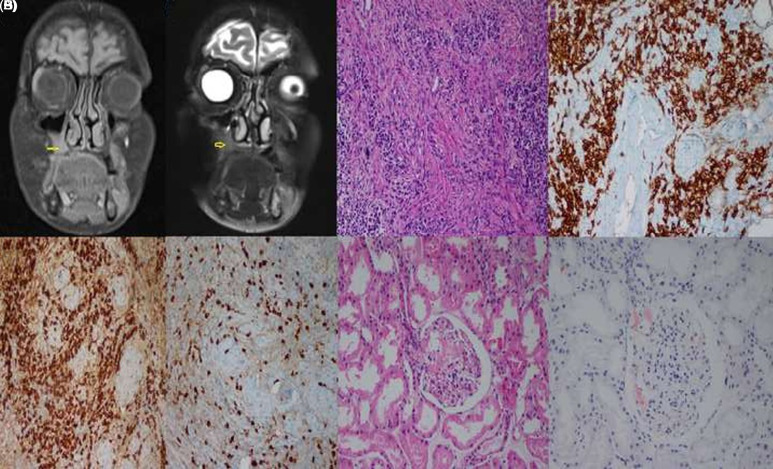

Occurrence of 2 Uncommon Findings in a Patient With Immunoglobulin G4-Related Disease: Maxillary Sinus Involvement and AA (Amyloid A) Amyloidosis.